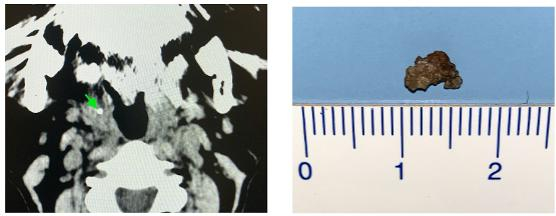

尽管扁桃体结石如此常见,但很少有人会因为它去医院看医生。医生通过仔细地查看扁桃体,或者通过内镜检查,可以很容易诊断扁桃体结石。也有很多人是因为口腔或者其他疾病,在做头颈部CT检查时才偶然发现。

CT检查发现的扁桃体结石[3]